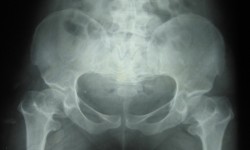

CHONDR ECTODERMAL DYSPLASIA (Ellis-Vancreveld syndrome)

By Admin | September 25, 2013 - 5:31 am | Musculoskeletal, Skeletal Dysplasias

Fig.3